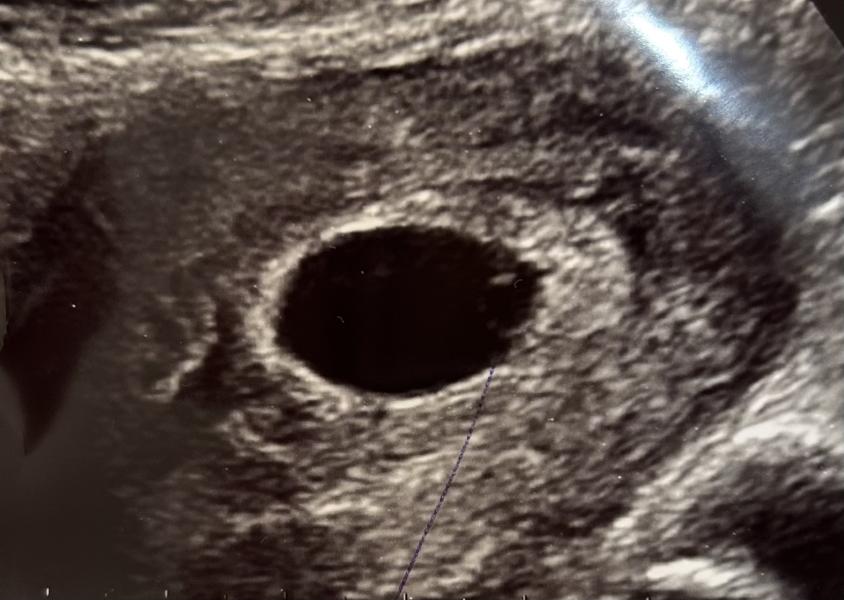

Что имеем пя 17,5

Жм 4,2

Эмбриона нет(

По узи 5 Нед 5 дней, на прошлом узи неделю назад не было еще жм. Врач сазала так то размер соответствует сроку узи. (5,5)